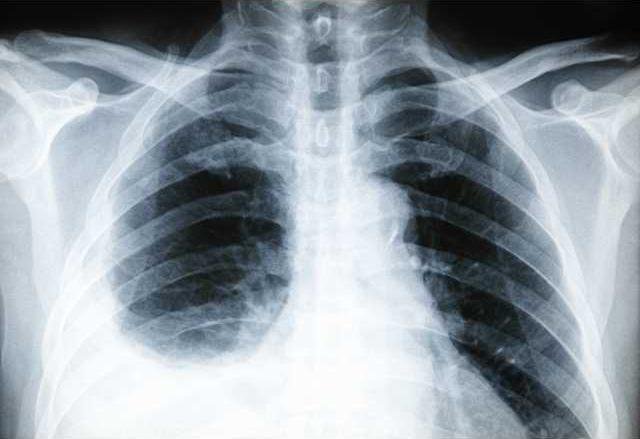

Pleurisy is inflammation of the membrane between your lungs and ribs, or pleura. The condition, which makes breathing both difficult and painful, often mimics the symptoms of a heart attack.

In a healthy body, the double-layered pleura lines the outside of the lungs and inside of the rib cage with a lubricating fluid in between its layers. When pleurisy happens, the tissue layers become inflamed and/or the fluid changes in consistency or amount.